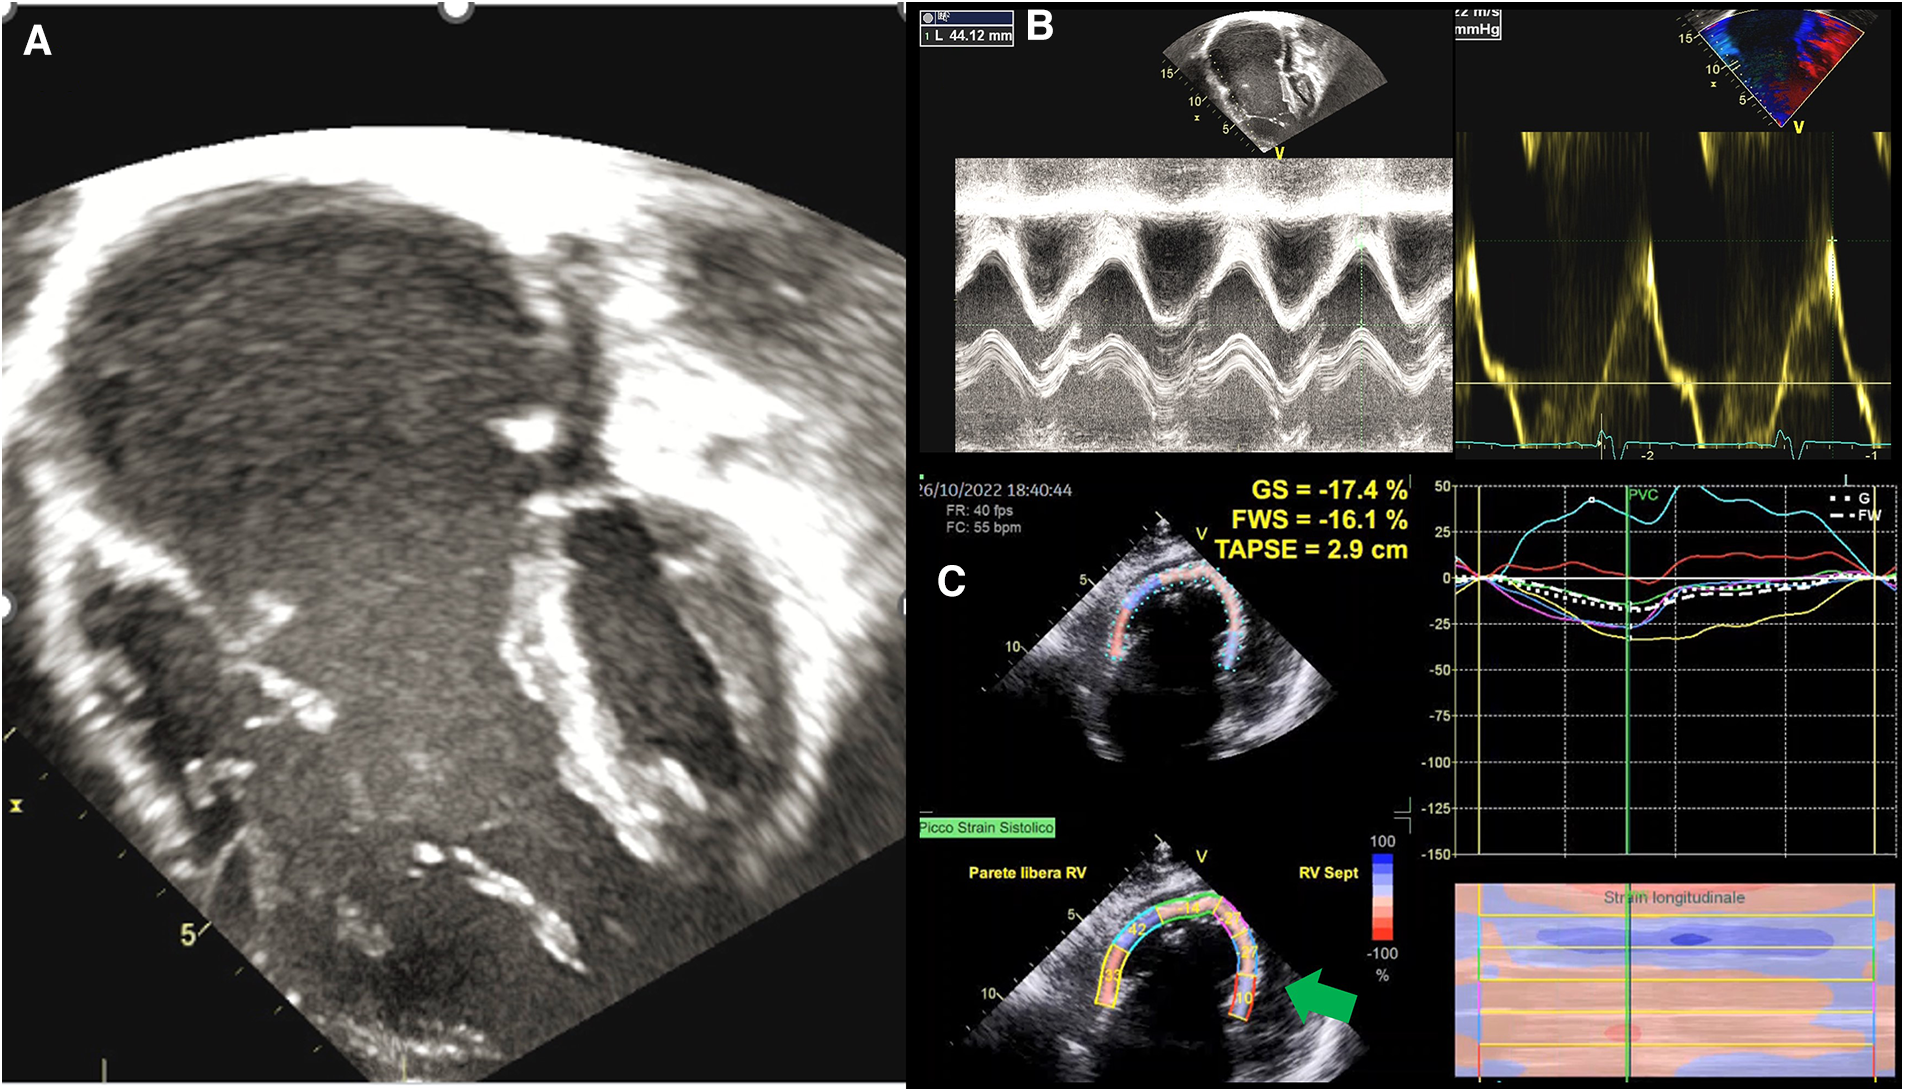

The evaluation of RV volumes and function by echocardiography is often difficult due to the retrosternal position of the RV and its complex geometry (62). This is particularly true in patients with EA, where the morphological abnormalities of the RV and the altered loading conditions (i.e., volume overload due to tricuspid regurgitation) further challenge this assessment (Figure 2). Most of the conventional echo parameters used to assess RV function may therefore be unreliable (63). In a small study of 16 EA's patients, measurement of fractional area change (FAC) was unfeasible due to difficulties in detecting the endocardial border (64). However, in another study including only young and unrepaired EA patients (n = 50) FAC assessment was feasible in the whole cohort (65). The authors found that this functional index also had prognostic significance, being the only predictor of progressive disease along with right atrium peak systolic strain (RA-PALS) (65). The RV-FAC is the expression of the contraction of the obliquely oriented fibers. This data confirms that the longitudinal function may be compromised early in EA patients, with an increased compensatory circumferential deformation reflected by FAC (65).

Figure 2

Functional assessment in ebstein anomaly. (A) EA as visualized by 2DE; (B) standard echocardiographic parameters to assess RV function, such as TAPSE an S’ wave, are increased in EA because of volume overload; (C) GLS analysis shows that the RV in EA is “atrialised” not only morphologically, but also functionally, as basal and medial septal strain values (green arrows) are positive in systole, thus behaving as an atrium. EA, ebstein anomaly; 2DE, two-dimensional echocardiography; TAPSE, tricuspid annular plane systolic excursion; GLS, global longitudinal strain; RV, right ventricle.